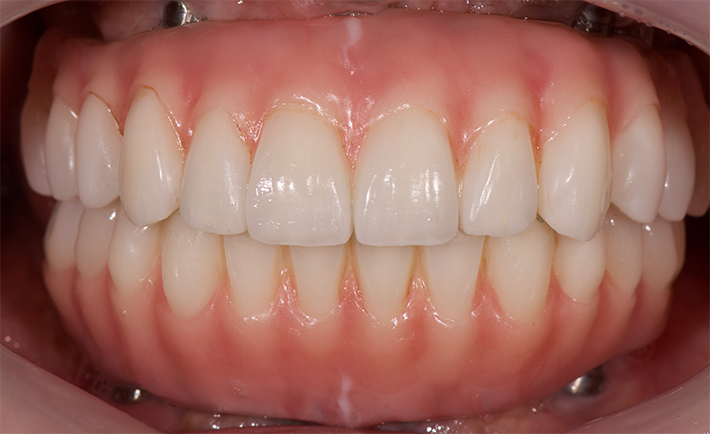

術前写真

最終補綴 (上下顎:フルジルコニアタイプ)

不自然な白い歯はカッコ悪い。白い中にも自然な透明感を求め、患者さんの笑顔を最大限に引き出す事が出来る完全オーダーメイドの補綴物を、患者さんの意見を聞きながら丁寧に作り上げております。